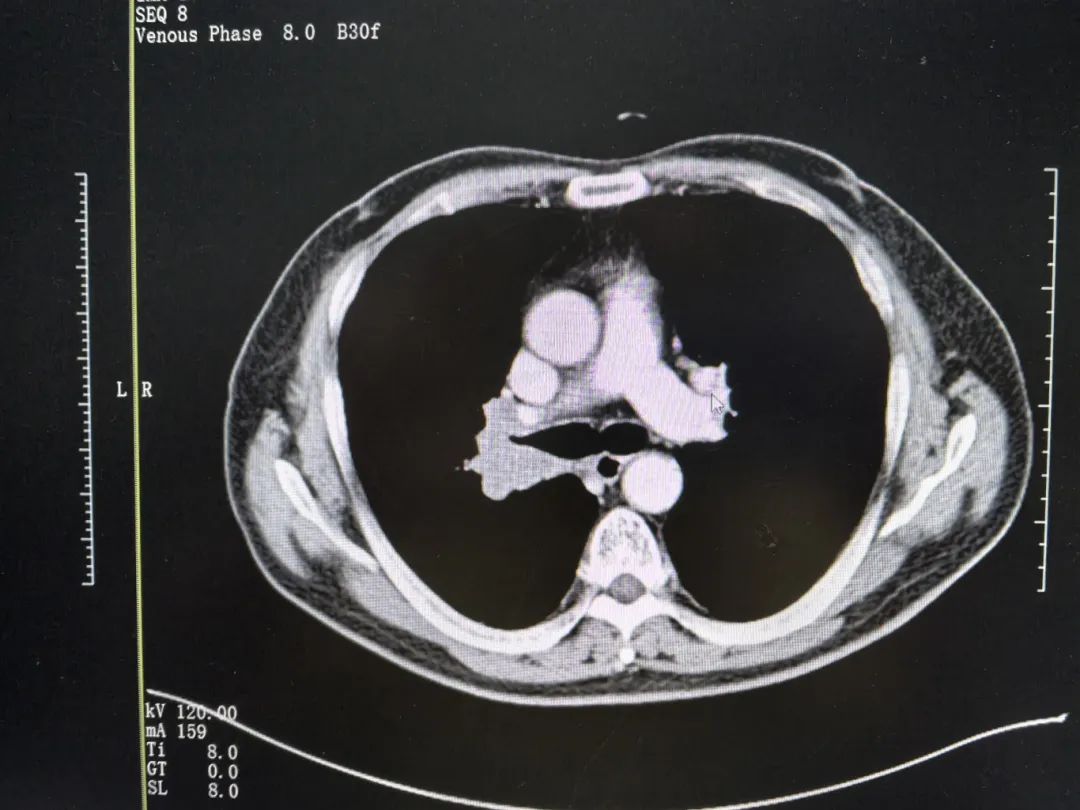

右肺门区有4.3x3.8x2.5cm的占位、邻近上叶各段支气管受压狭窄、双肺多发磨玻璃结节、纵膈和右侧肺门多发肿大淋巴结,较大者约3.4x2.4cm……结合金叔既往病史及入院检查结果,医疗一科石海燕医生立即申请多学科会诊,经过讨论与评估后,考虑到其小细胞肺癌治疗中缓慢进展,且肿瘤靠近大血管,手术风险高,遂建议进行局部治疗如放疗以及更换全身抗肿瘤方案。

▲治疗前影像结果